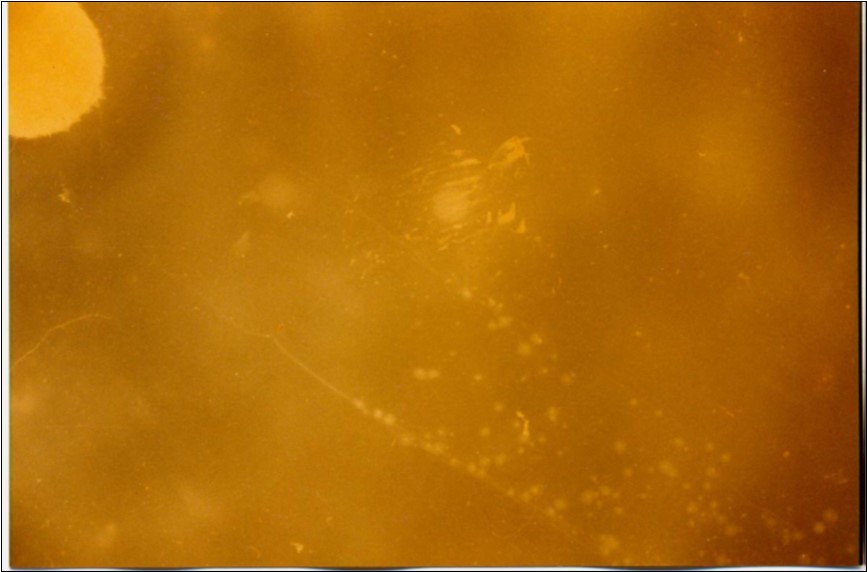

No mycoplasma was isolated from slaughterhouse samples. Three mycoplasma isolates were recovered from three out of six cases showing typical clinical signs and P.M. lesions. The isolates were identified as Mmm depending on cultural characteristics (Figure 1), digiton in test (Figure 2), and growth inhibition test.

Figure 1.Colonial morphology of Mmm of recent field isolate grown on heart infusion agar after 3 days of incubation (×40).

Although no advanced techniques like PCR were used to identify the isolates, procedures used in this study were quite enough to confirm the incidence. Affected animals with CBPP were diagnosed based on the clinical signs, the PM findings, the typical histopathological picture in addition to the isolation of the causative agent and its subsequent identification using cultural and biochemical procedures. Identification of the isolates was confirmed by the growth inhibition test as recommended in OIE manual 10. The histopathological sections of diseased lungs, from which Mmm (SC) was isolated, showed typical histopathological picture of CBPP. The CBPP lesion comprises abronchiolar necrosis and oedema which progress rapidly to an exudative serofibrinous bronchiolitis with extension to the alveoli and uptake of alveolar fluid into tissue spaces 17, lymphatic vessels and ultimately septal lymphatics 18. With stasis, lymphatic vessels become thrombosed and ultimately fibrosed 19. The histological section of the lung in acute stage of the disease showed odema in the lymphatics of the interlobular septa and interstitial tissue and massive infiltration of fibrin, macrophage and neutrophils into the alveolar lumen 20. Also there was presence of lymphocytes and alveolar macrophages around the lymphatic vessels and septa margin 21. These findings supported the isolation results and gave additional evidence for the diagnosis of the disease.